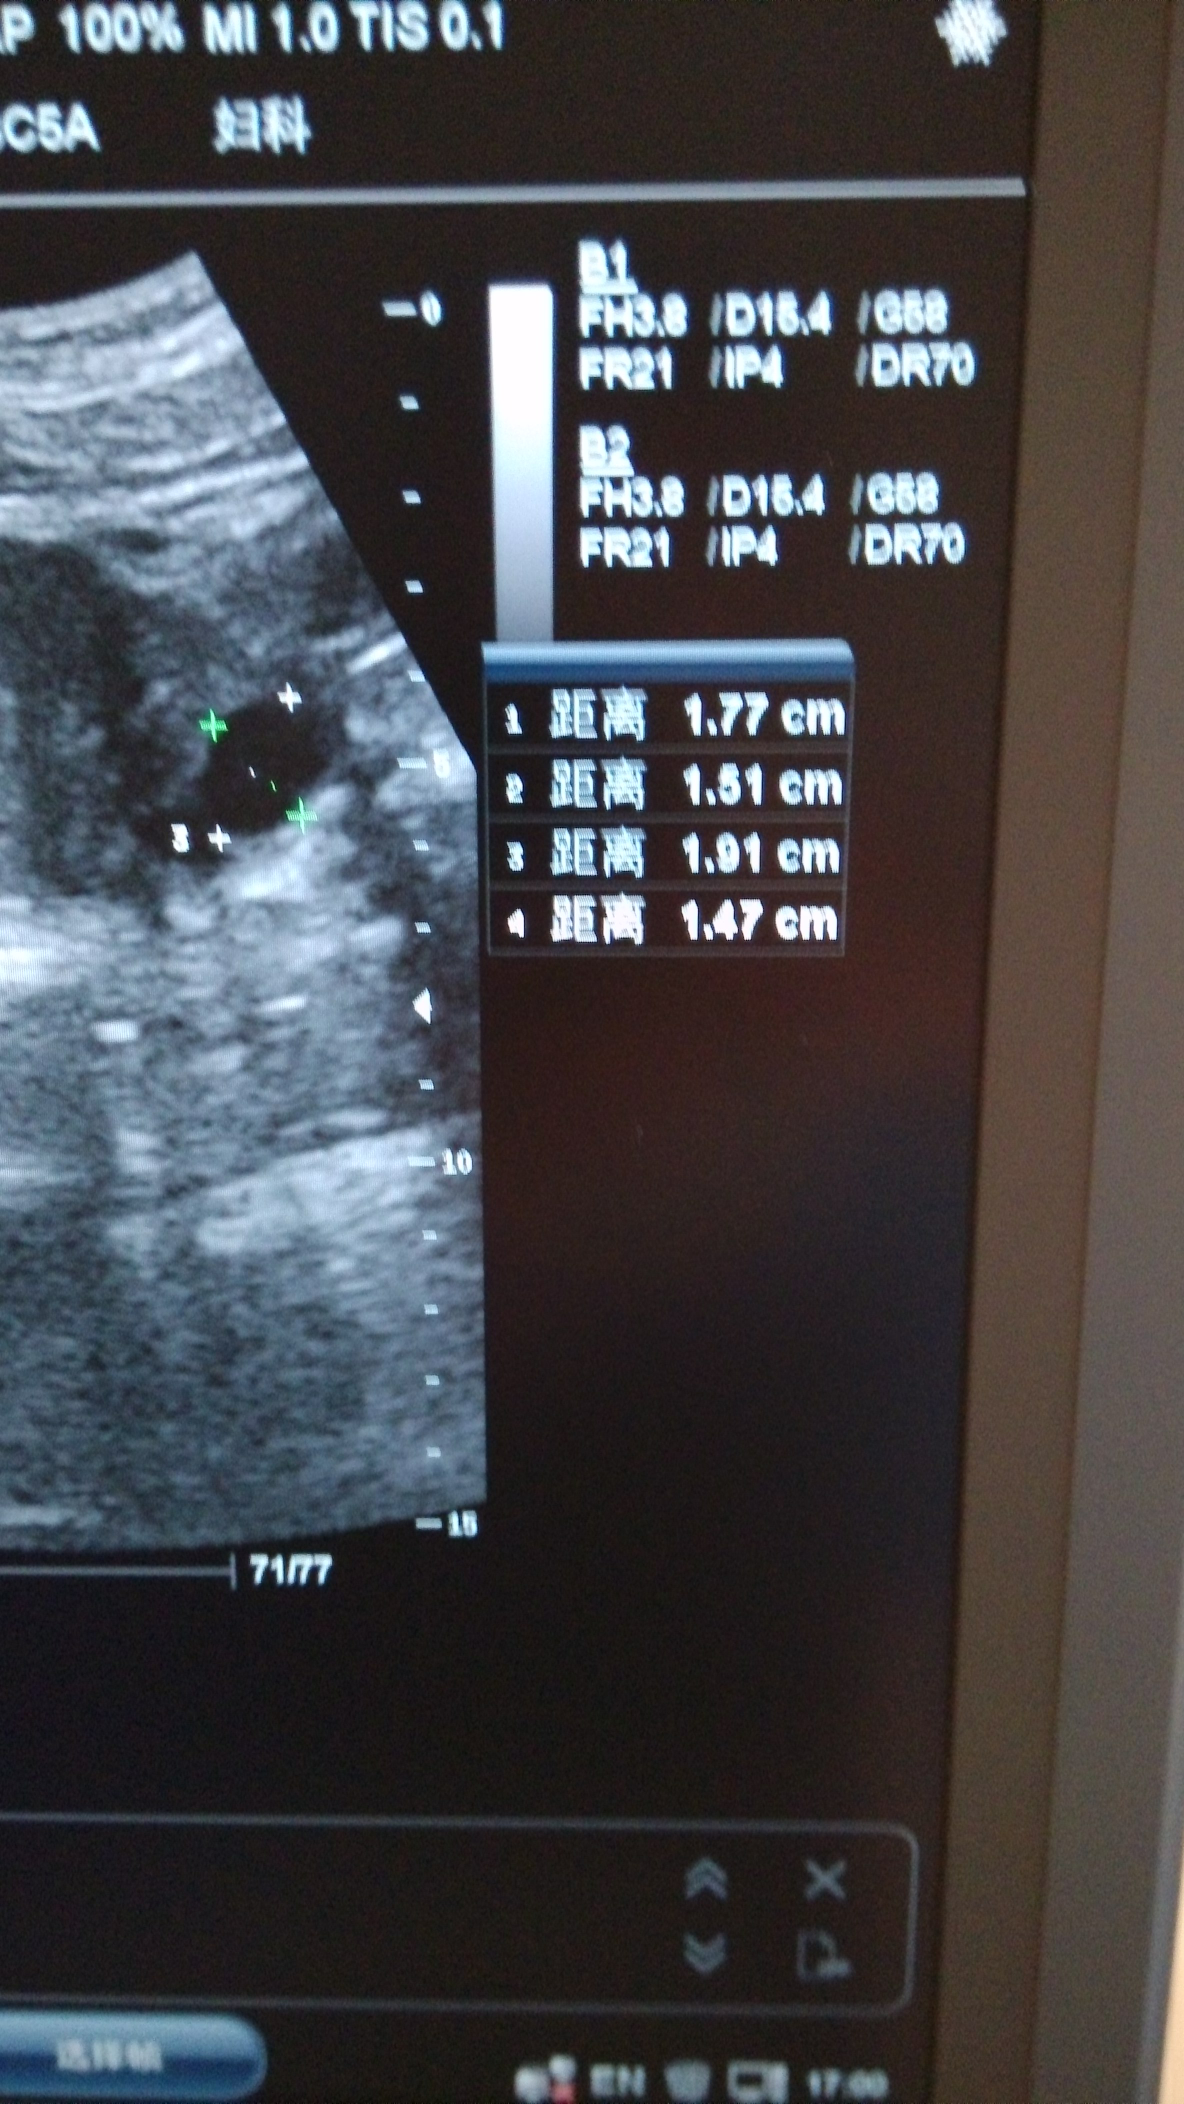

这个大小算正常吗怎么就是………